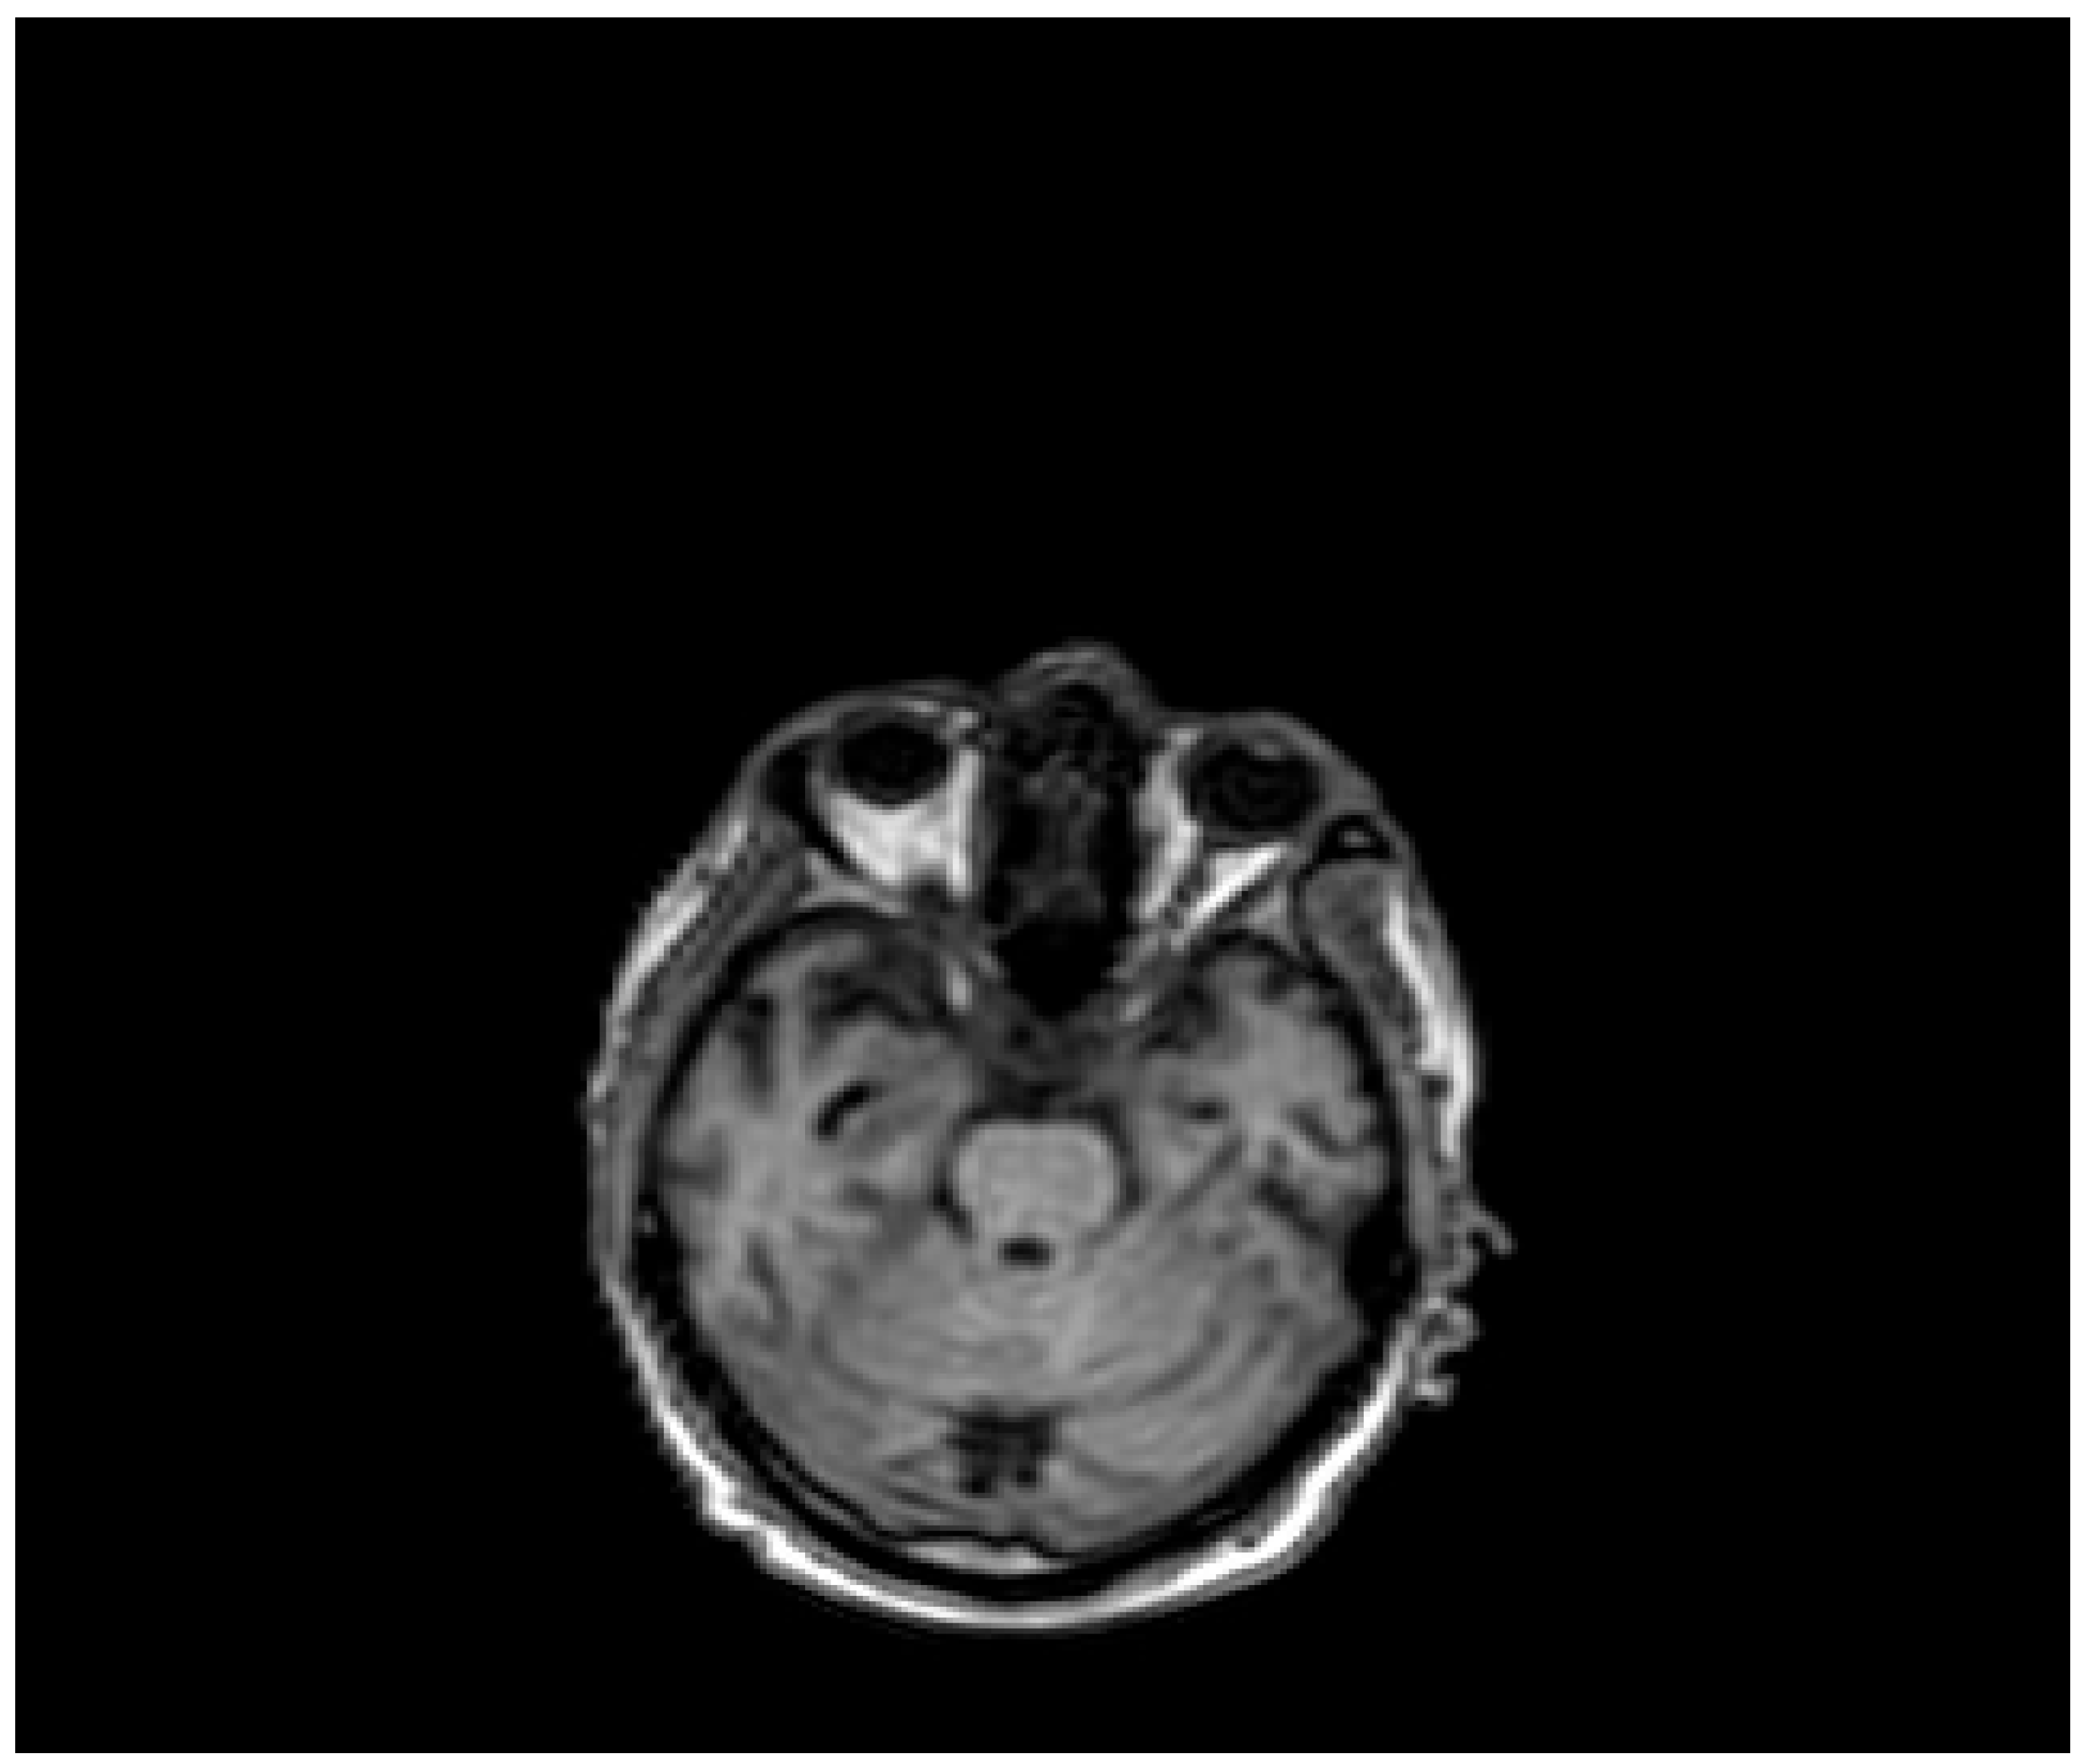

| Pt 7, M, 71, 2025 | HHD, cognitive involutional syndrome | High fever, headache, confusion, worsening motor difficulty with lower limb weakness | +/+ | Neg | Neg | Neg | ICH of the occipital horns of the lateral ventricles (Figure 2) | Diffuse meningoencephalitis, with involvement of the cauda extremity roots. ICH of the occipitopolar and bihemispheric mid-posterior cingulate sulci, the left temporoparietal carrefour, and the fourth ventricle, occipital horns, and pericerebellar cistern. Posterior dorso-lumbo-sacral, anterior dorso-lumbar (up to L1), and sacral epidural hematoma (Figure 3 and Figure 4) | DEX, Igs | Gradual clinical improvement, however lower limb weakness persisted | Transferred to a rehabilitation facility 34 days after hospital admission. | |

Figure 4.

Evidence of ICH on brain MRI (Table 1, patient 7).

Three male patients with a median age of 71 years (range 68–74), presented ICH associated with WNE (Table 1, patient 2, 7, 9). Two male patients, the first 74-year-old (Table 1, patient 2) suffering from arterial hypertension and the second 68-year-old (Table 1, patient 9) suffering from diabetes mellitus and post-ischemic dilated heart disease, died after 13 and 21 days, while the third patient (Table 1, patient 7) was transferred to a neuromotor rehabilitation facility after 34 days of hospitalization. This patient, before admission to the hospital, presented age-related brain involution symptoms and suffered from chronic hypertensive heart disease. The reasons for admission to the emergency room were worsening motor difficulties with weakness in the lower limbs, a rapidly worsening state of confusion, high fever, and an episode of hypertensive peak. Repeated studies of the brain and spinal cord, using computed tomography (CT) scans and magnetic resonance imaging (MRI), have documented a very complex picture, characterized by diffuse meningoencephalitis, with a diffuse flogistic involvement of the pachy-leptomeninges and the equine cauda roots, blood deposits in the occipitopolar and bihemispheric mid-posterior cingulate sulci, the left temporoparietal carrefour, the fourth ventricle and occipital horns and the pericerebellar cistern. There was also evidence of a diffuse posterior dorso-lumbo-sacral, anterior dorso-lumbar (up to L1) and sacral spinal cord epidural hematoma. Diffuse hemosiderin coating was present on the dural surface in the dorso-distal posterior lumbo-sacral and anterior lumbo-sacral regions, as well as at the anterior 8th-10th level. Serology for WNV was positive, while WNV RNA testing in CSF, blood, and urine was negative. Treatment included two 5-day cycles of high-dose immunoglobulins and the use of dexamethasone (Table 1, patient 7).